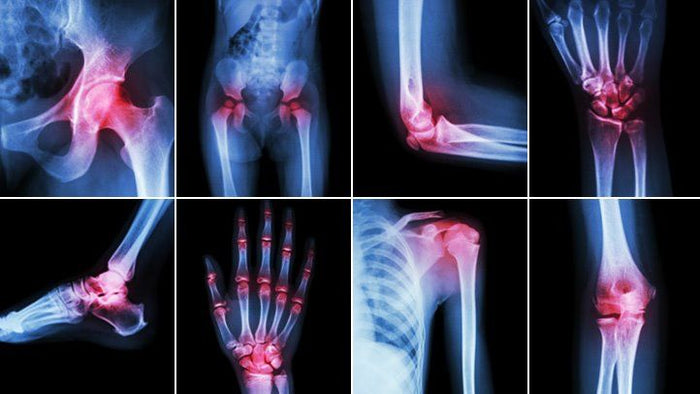

Compression force (or compressive force) occurs when a physical force presses inward on an object, causing it to become compacted. This occurs throughout our daily life as we walk, run and carry heavy loads. Compressive forces are pushing down on our body, specifically on the lower part of our body where the compression is felt most (Tekscan). Compression can have negative effects on lower extremities causing bone damage, fatigued limbs and flat feet.